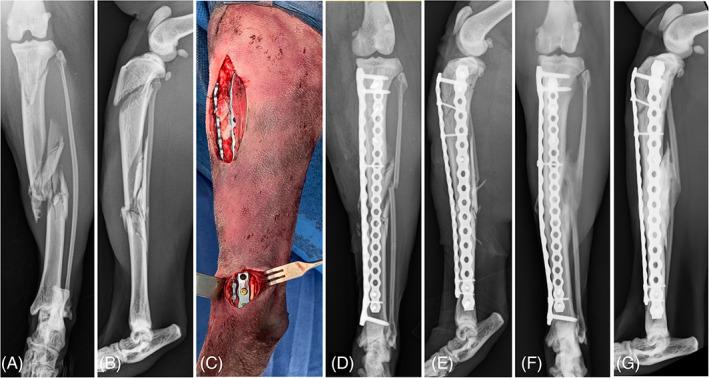

To summarize and discuss peer-reviewed studies on minimally invasive osteosynthesis (MIO) of long bone, physeal, and articular fractures in dogs and cats.

More than 40 MIO articles have been published in the last 15 years, but most studies had small numbers, lacked control groups, and used limited outcome measures. Studies generally showed that MIO was feasible in dogs and cats with low complication rates. The current evidence does not demonstrate superior bone healing or functional outcomes with MIO when compared to standard methods. Although treatment principles, case selection, and techniques varied depending on the anatomical location, there were no salient differences in complication rates among long bones, physeal, and articular fractures treated by MIO.

The current available evidence and the personal experience of the authors support MIO as a promising fracture management modality. MIO can yield excellent outcomes when applied in carefully selected cases, performed by surgeons experienced in the technique. We cannot, however, conclude that MIO is superior to open fracture stabilization based on the available evidence in veterinary literature. Randomized controlled studies are warranted to prospectively compare MIO with other osteosynthesis techniques and thereby validate its role in fracture management for dogs and cats.